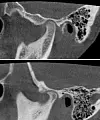

Øverst: Friskt kjeveledd på 14-årig jente. Nederst: 13-årig jente med kjeveleddsartrose. Her kan man se at sykdommen har forårsaket en formendring (nebbdannelse), slik at benet ikke lenger har en normal form. (Foto: Avdeling for kjeve- og ansiktsradiologi, UiO/OD)

Ofte opptrer muskelsmerter og sykdom i kjeveleddet samtidig. To relativt store røntgenstudier viste at mellom en tredjedel og en fjerdedel av ungdom med ansiktssmerter og kjeve har forandringer i kjevebenet som tilsvarer artrose.